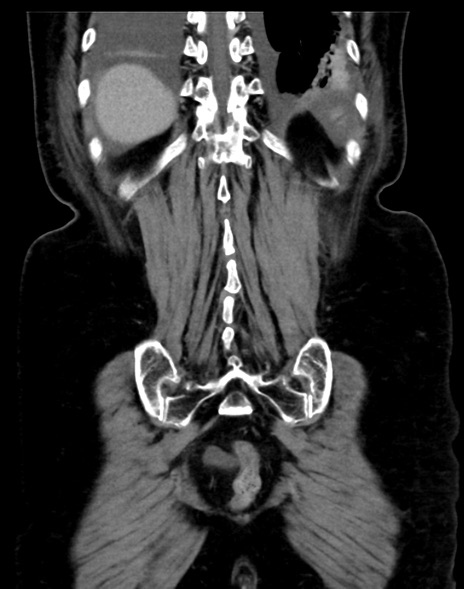

症例13 CT(冠状断像)1日半後